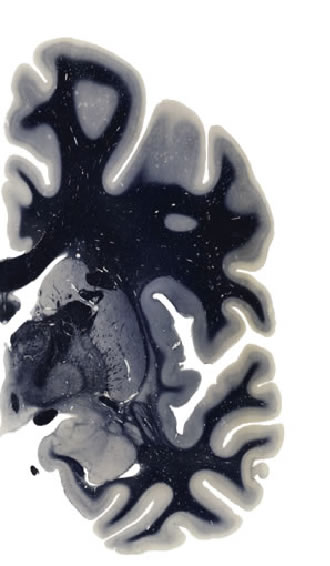

Frontal sections (Nissl) from the Atlas Brain: Gallery Slice Single

6,1 mm

Slice ID: r3-1171

Plate NR: ca 26-27

Position: 6,1 mm